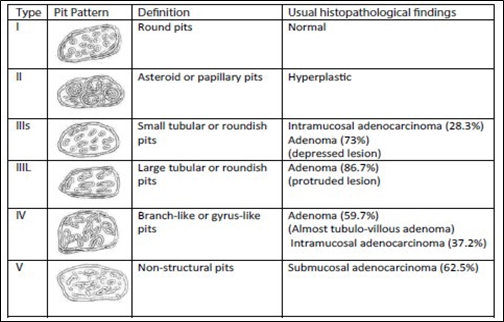

Kudo classifies adenomas into protruding (polypoid lesions), flat-elevated, and flat (Figure 8). Flat-elevated lesions are further divided into flat-elevated and flat-elevated with central depression. The flat type of lesion is subdivided into flat and depressed. In this classification, the flat type corresponds to the initial description of flat adenomas. within 2001, Kudo and colleagues morphologically analyzed approximately 20,000 colonoscopic lesions and determined that polypoid and non-polypoid lesions accounted for 55% and 45% of cases, respectively. Non-polypoid lesions are present in the proximal and distal regions of the colon in equal proportion, whereas polypoid lesions are more frequent in the distal colon [14, 15].

|

Fig. 8 Kudo classification of colonic neoplastic lesions [14, 15] Note: Pit pattern classification of colorectal neoplasia (Kudo et al.). I – Round pit (normal pit), II – asteroid pit, IIIS – tubular or round pit (smaller than the normal pit, i.e., type I), IIIL – tubular or round pit (larger than the normal pit, i.e., type I), IV – dendritic or gyrus-like pit, V – amorphous, nonstructured pit. |